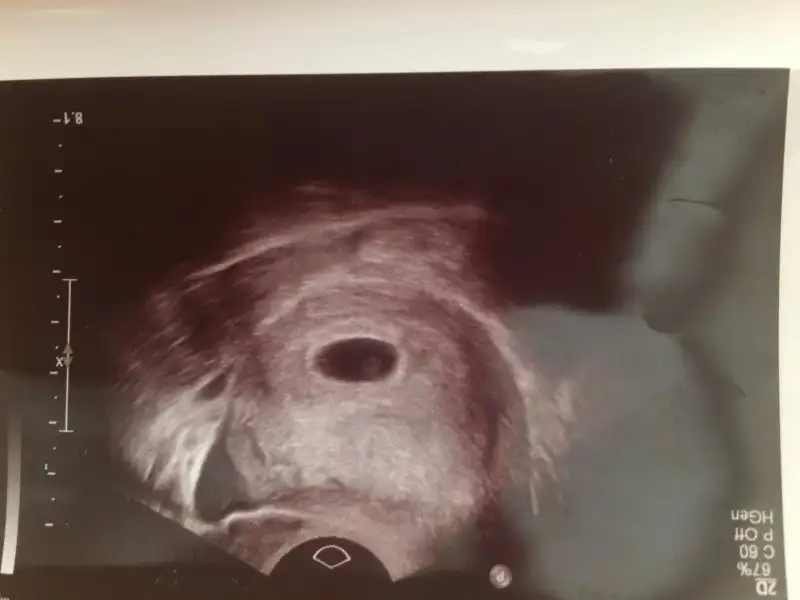

Birde benm şçin tahmin de bulunurmusunuz lütfen Vajinal ultrason la bakıldı bugün

Eklentiler

• IMG_3928.webp

IMG_3928.webp

20,3 KB · Görüntüleme: 200